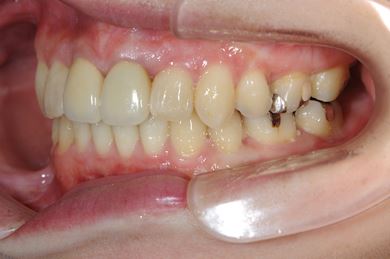

全顎矯正治療+セラミック治療

| 主訴 | 出っ歯 上顎前歯の並び | ||||||||||||||||||||||||||||||||

| 治療方針 | 上下歯牙がだいぶ前にでていて口が閉じづらい状態でした。なるべく金属が入っている歯を抜歯したいので、上下左右第二小臼歯を抜歯して、その隙間を利用して、口元をさげていきました。また、口元を最善の状態にうるために、抜歯スペースを使用したあと、上下左右のインプラントアンカー(釘)でより一層口元を後ろにさげていきました。ただの抜歯ケースよりだいぶ口元が下がっているのが分かります。抜歯したスペースががたつき(叢生量)で使用してしまう場合には、このような方法でより口元をさげることができます。お顔立ちがとてもよくなりました。とても協力していただけたので、しっかりと良くなることができました。 | ||||||||||||||||||||||||||||||||

| 治療内容 | 唇側矯正(ホワイト・上下左右第二小臼歯抜歯・上下インプラントアンカー)、オールセラミッククラウン1本(オールセラミック用土台1本)、ジルコニアフレームオールセラミッククラウン1本 | ||||||||||||||||||||||||||||||||